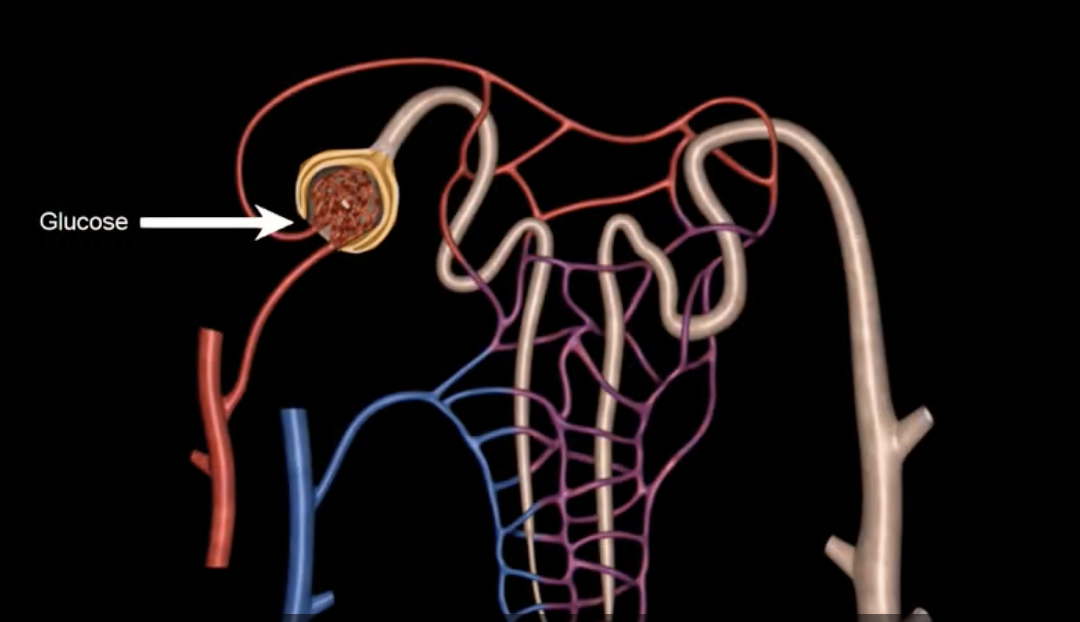

golmerular filtration

pressure driven movement of fluid and small solutes out of blood to form filtrate (ions, glucose, amino acids, nitrogenous wastes)

green: renal corpuscle

purple: renal tubule

blue: glomerulus

orange: Bowman’s capsule

bowman’s capsule

orange

proximal convoluted tubule

green